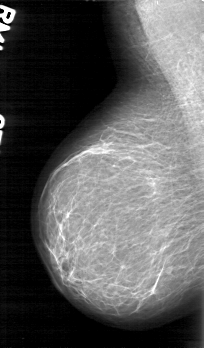

Digital Database for Screening Mammography

Volume: benign_09 Case: D-4045-1

D_4045_1.LEFT_MLO

LEFT_MLO LINES 5266 PIXELS_PER_LINE 3481 BITS_PER_PIXEL 12 RESOLUTION 43.5 OVERLAY